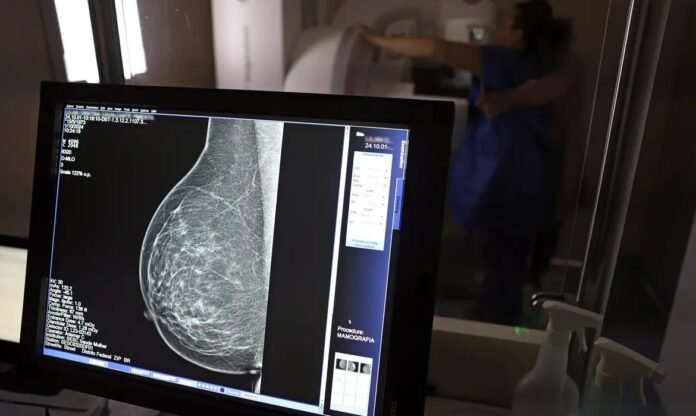

A ferramenta processou mamografias digitais que haviam sido consideradas normais nos exames iniciais.

A ferramenta analisa características do tecido mamário e densidade para estimar a chance de surgimento de um câncer intervalado.